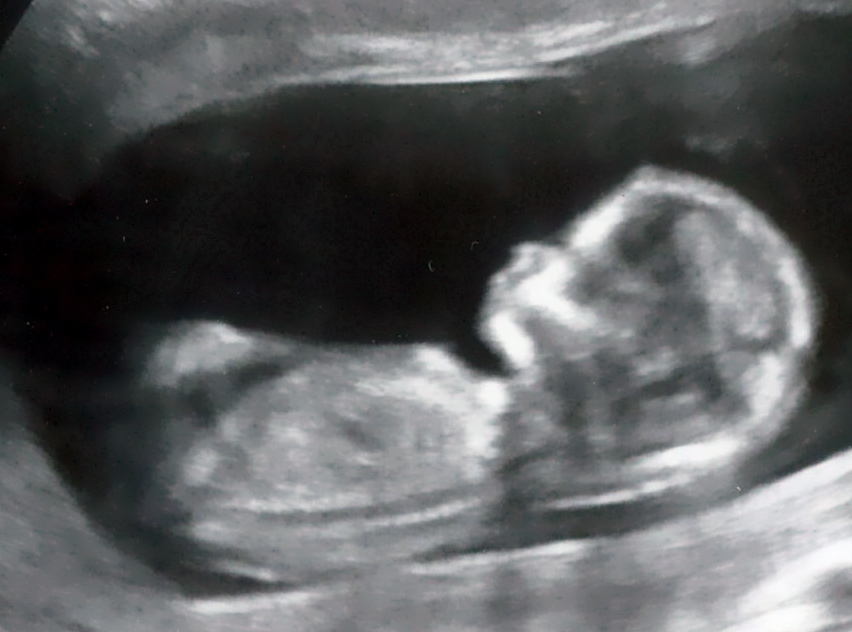

At first, it didn’t really seem all that real to me. First trimester was not at all enjoyable. It seemed like it was all symptoms and no point to them whatsoever. For all I knew, I was simply suffering from multiple chronic issues including indigestion, constant nausea (wouldn’t it be nice if it were ACTUALLY confined to only mornings?), loss of fitness, general fatigue, and unexplainable weight gain. The excitement was virtually non-existent… except for when I was talking to Kerry, James’ mother and Baby Snare’s grandma-to-be! I did have the 12 week ultrasound (I told my husband that my only goal for that ultrasound was simply to get proof that there actually was a baby inside me!) but whilst it had its magical moments, after it was over it still felt like I was simply watching someone else’s baby video.

(16 weeks)